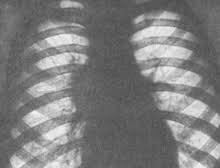

[caption id="attachment_2818" align="alignright" width="320"] Бронхоаденит на рентгене[/caption]

При рентгенологическом обследовании врач увидит в органах дыхания патологические образование – мелкие очаги воспаления в виде гнойничков и гранулем. Бронхоаденит характеризуется на снимке при рентгенографии изменением формы корня легкого, его деформацией, расширением или искривлением. Изменения крови аналогичны определяемым при острой туберкулезной инфекции.   На основании клинических и рентгенологических проявлений врач делает заключение и ставит корректный диагноз, после чего подбирает оптимальную схему лечения.